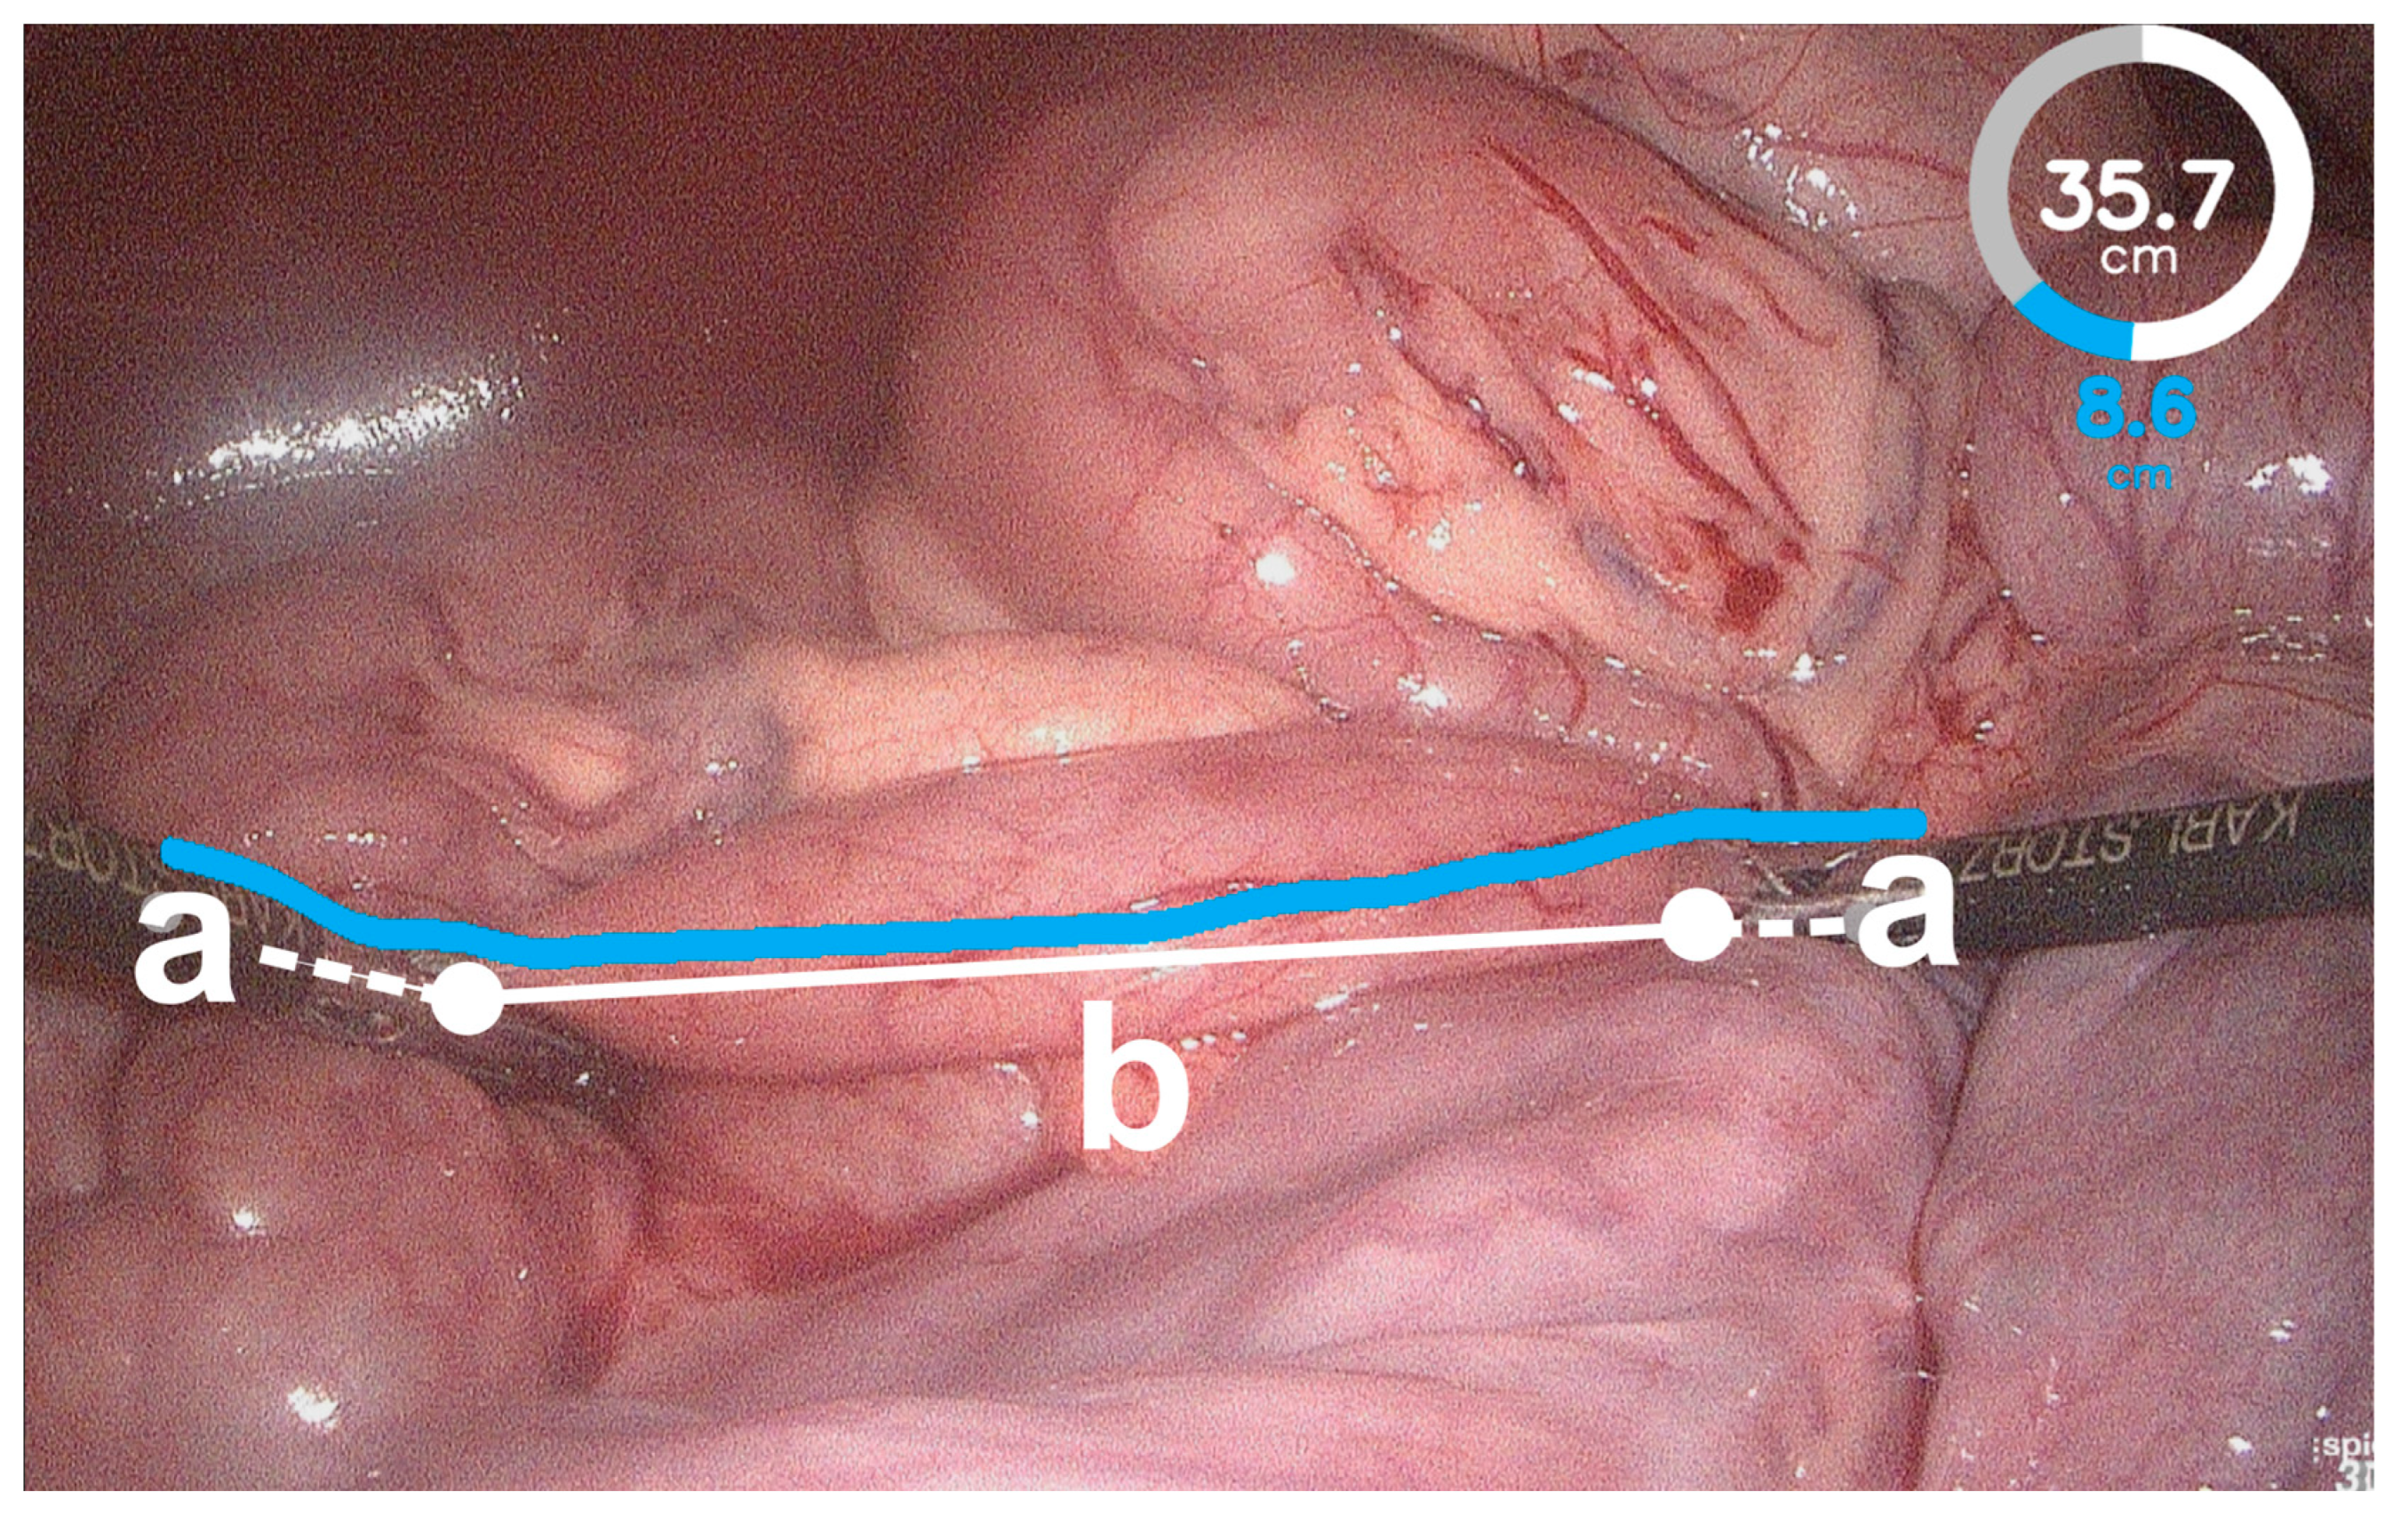

- Wagner, M.; Mayer, B.F.B.; Bodenstedt, S.; Stemmer, K.; Fereydooni, A.; Speidel, S.; Dillmann, R.; Nickel, F.; Fischer, L.; Kenngott, H.G. Computer-Assisted 3D Bowel Length Measurement for Quantitative Laparoscopy. Surg. Endosc. 2018, 32, 4052–4061. [Google Scholar] [CrossRef]

- Wagner, M.; Mayer, B.F.B.; Bodenstedt, S.; Kowalewski, K.F.; Nickel, F.; Speidel, S.; Kenngott, H.G.; Müller-Stich, B.P. Comparison of Conventional Methods for Bowel Length Measurement in Laparoscopic Surgery to a Novel Computer-Assisted 3D Measurement System. Obes. Surg. 2021, 31, 4692–4700. [Google Scholar] [CrossRef]